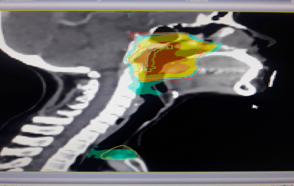

The challenges of treating head and neck cancer in the older population

The number of patients with cancer aged 65 years and older will increase in next several decades. Approximately 25% of patients with head and neck cancer (HNC) are aged 70 years and older.